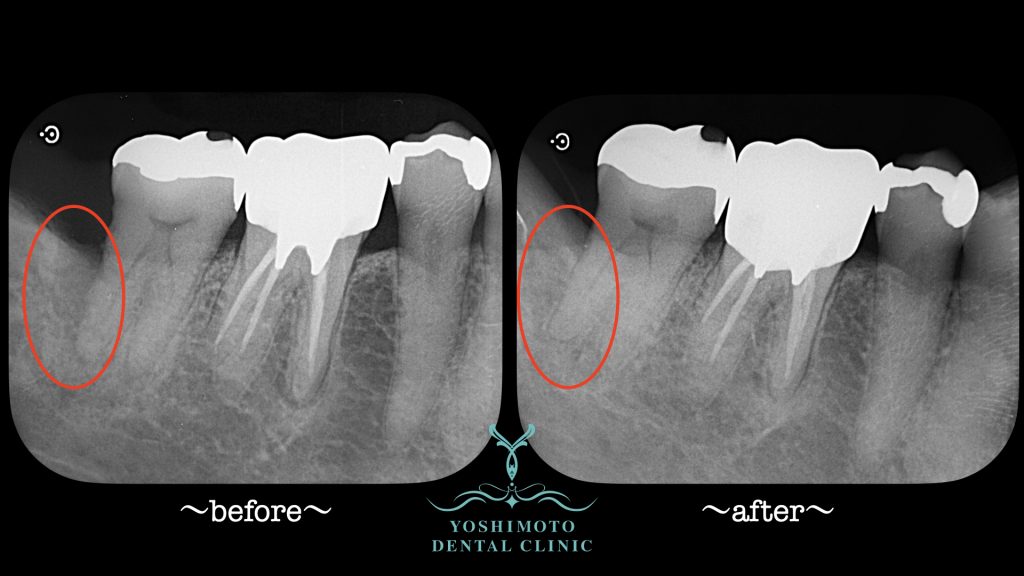

⇧術前術後のレントゲン写真の比較です。

骨が再生しているのがわかると思います。